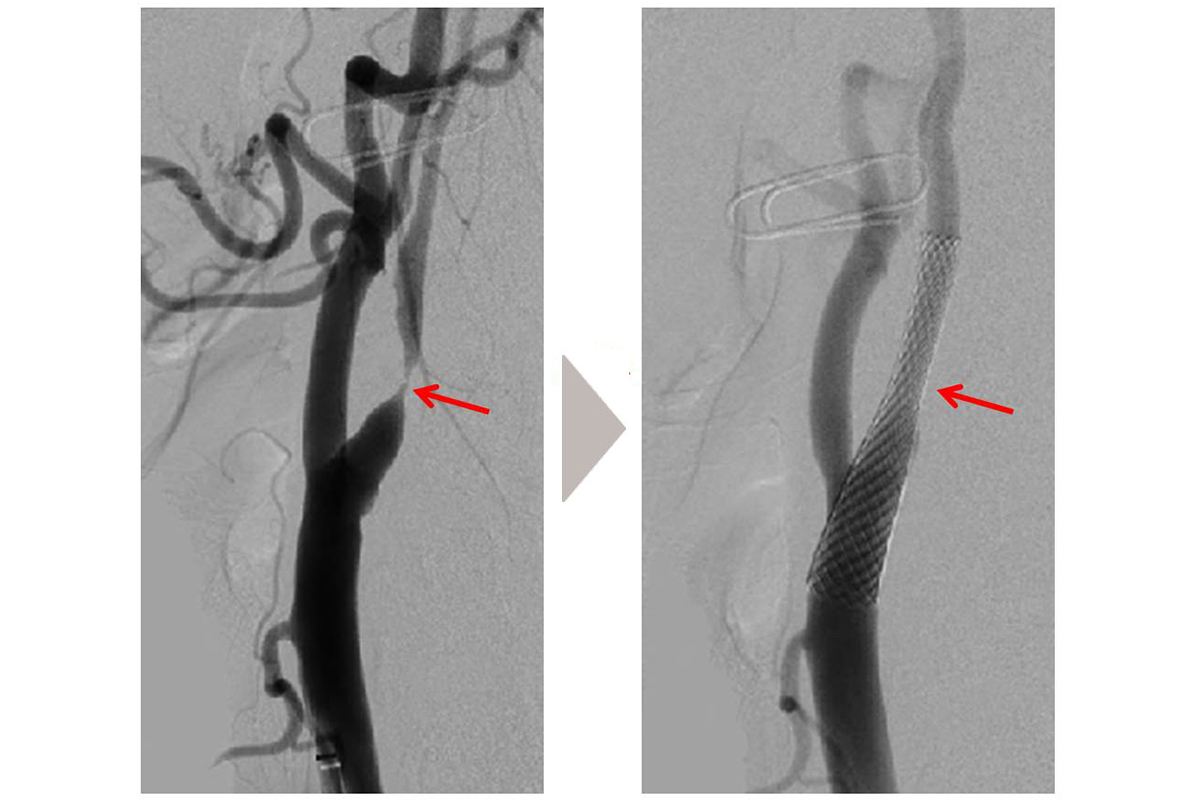

脳神経外科 概要 スタッフ紹介 疾病・治療 疾病・治療 一覧を見る 脳卒中の急性期治療〜脳梗塞に対するカテーテル治療〜 脳外科医がお話しする特発性正常圧水頭症 診療科・部門 診療科 内科 肝臓内科 糖尿病センター 脳神経外科 整形外科 リハビリテーション科 眼科(府中アイセンター) 泌尿器科 泌尿器科(透析センター) 看護部 看護部 薬剤科 薬剤部 診療技術部 放射線室 臨床検査室 リハビリテーション室 栄養管理室 臨床工学室 感染制御室・医療安全管理室 感染制御室 医療安全管理室 地域連携・在宅療養支援部 地域医療連携室 医療福祉相談室 管理部 医療情報課 総務課 府中病院附属きらら保育所